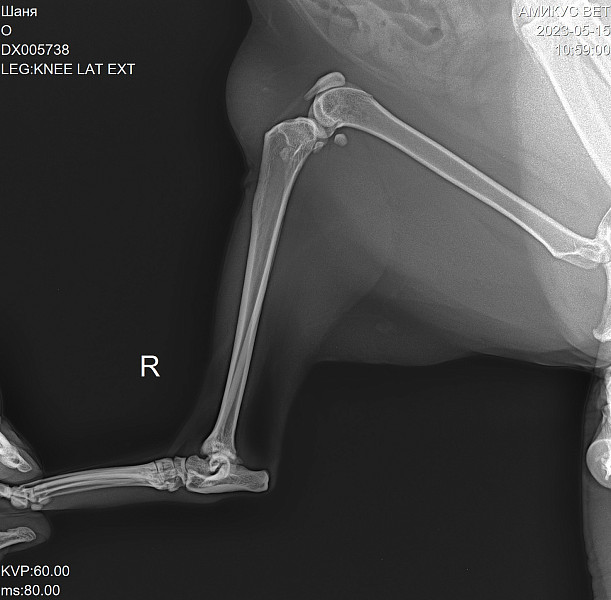

Лечение суставов у кошки

Лечение суставов у кошки 111 фотографий